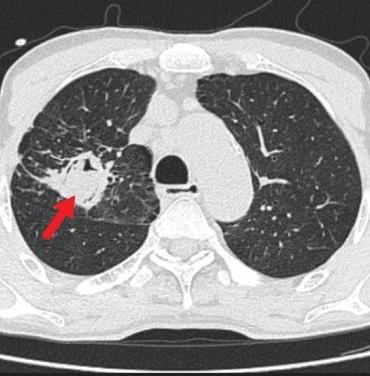

• 侵袭性肺真菌病的支气管镜表现及介入治疗效果

2025, 31(9):81-90. DOI: 10.12235/E20250317

摘要 (112) HTML (56) PDF 6.06 M (77) 评论 (0) 收藏

摘要:目的 探讨侵袭性肺真菌病(IPFD)的支气管镜表现,并评估介入治疗的安全性和疗效。方法 回顾性分析2018年5月12日-2025年5月12日于该院行支气管镜检查的35例IPFD患者的临床资料,观察IPFD的支气管镜表现及介入治疗效果。结果 共收集35例患者临床资料。其中,男22例,女13例,患者年龄(53±14)岁。基础疾病包括:血液系统恶性肿瘤10例,长期应用糖皮质激素者5例,2型糖尿病者4例,肺部恶性肿瘤2例,器官移植1例。胸部CT显示:肺部病变累及单肺叶者19例,累及多肺叶者16例。支气管镜下表现主要为:黏膜充血水肿29例(82.9%)、坏死物堵塞管腔22例(62.9%)、大量黏稠脓性分泌物17例(48.6%)、支气管部分狭窄或闭塞16例(45.7%)、黏膜坏死9例(25.7%)、黏膜出血5例(14.3%)、真菌球3例(8.6%)。其中,32例(91.4%)接受全身性抗真菌治疗,17例(48.6%)接受支气管镜局部两性霉素B灌注治疗,10例(28.6%)采用活检钳钳除病灶,6例(17.1%)采用冷冻探头冻取病灶,4例(11.4%)接受氩气刀治疗。28例(80.0%)临床症状明显改善,肺部影像学病灶缩小或消退;4例(11.4%)病灶稳定;3例(8.6%)未完成治疗。结论 IPFD多见于免疫抑制宿主,支气管镜常表现为:坏死物堵塞管腔、伴脓性分泌物、支气管管腔狭窄和局部黏膜充血水肿或坏死。全身抗真菌药物联合支气管镜下介入治疗,安全性高,且疗效好。